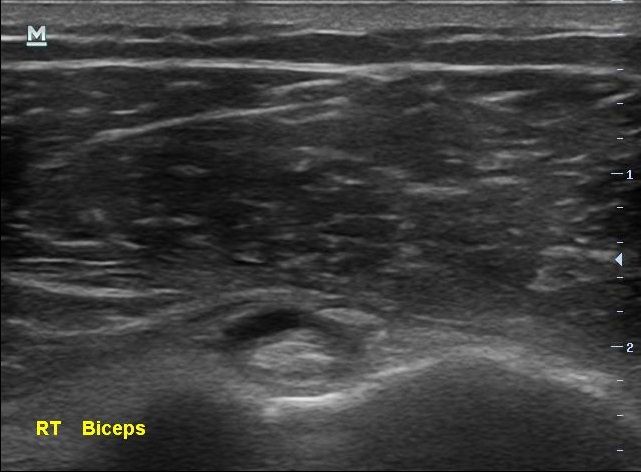

골프 중독으로 어깨 힘줄 끊어진 환자 이야기 (당산정형외과 당산역정형외과 당산동정형외과 여의도정형외과 합정정형외과 목동정형외과 영등포정형외과 영등포구청정형외과 선유도정형..

당산정형외과 당산역정형외과 당산동정형외과 여의도정형외과 합정정형외과 목동정형외과 영등포정형외과 영등포구청정형외과 선유도정형외과 도수치료 박상준의원)안녕하세요 박상준원장입니다. 오늘은 얼마전에 어깨 통증으로 방문한 환자 이야기를 해볼까 합니다. 나 : 어디가 불편해서 오셨어요?환자 : 어깨가 아픕니다.나 : 아픈지 얼마나 되셨나요?환자 : 그게.... 대략 3년정도 되었네요 꽤 오랜시간 어깨가 아팠다는 환자분.... 나 : 아프신지가 꽤 오래되었네요? 병원은 처음 오신 거에요?환자 : 네 아프지는 오래되었는데 ... 병원은 처음이네요... 제가 아픈걸 잘 참아서요... 아픈걸 잘 참아왔다는 환자분..... 그런데 나 : 병원 방문을 결심하신 이유가 있나요?환자 : 그동안은 그럭저럭 지냈는데.... 몇주전..